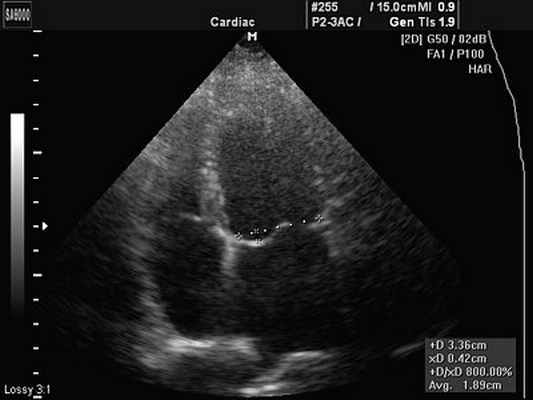

В диагностике, помимо анамнеза, результатов клинического осмотра и наблюдения, наибольшее значение приобретает ультразвуковая эхокардиография (ЭхоКГ), которая практически не имеет противопоказаний, допускает повторные исследования в динамике и позволяет наглядно визуализировать аневризму с точной оценкой ее характеристик. В качестве уточняющей диагностики, – обычно для выявления и исследования сопутствующих аномалий и пороков, – дополнительно могут быть назначены чреспищеводное УЗИ, КТ, катетеризация сердца.

В больнице «Герцлия Медикал Центр» применяются все современные методы кардиологической диагностики, позволяющие безошибочно определить наличие аневризмы и ее осложнений. Профилирующим методом является эхокардиографическое исследование (через грудную стенку или чрезпищеводное исследование). Помимо оценки состояния миокарда и его функциональной способности, эхокардиография позволяет определить наличие и размеры пристеночного тромба. При соответствующих показаниях пациенты клиники проходят также томографическую визуализацию сердца (кардио-КТ), изотопное сканирование, мониторинг сердечного ритма и катетеризацию коронарных сосудов.

Но наиболее эффективным и информативным методом, при диагностике АМПП, является чреспищеводное эхокардиографическое исследование (ЧП-ЭхоКГ). Метод основан на обычном ультразвуковом исследовании, во время которого пациенту через пищевод вводят ультразвуковой датчик. Это позволяет получать наиболее точные данные о работе сердца так как отсутствуют помехи в виде ребер, подкожного жира и слоев мягких тканей.

Для предотвращения рвотного рефлекса применяется местная анестезия глотки и языка. При введении датчика на глубину около 10 см, пациенту необходимо его проглотить. Процедура проводится на голодный желудок и длится 5-15 минут.

Для ЧП-ЭхоКГ существует протокол, по которому необходимо изучать следующие параметры: